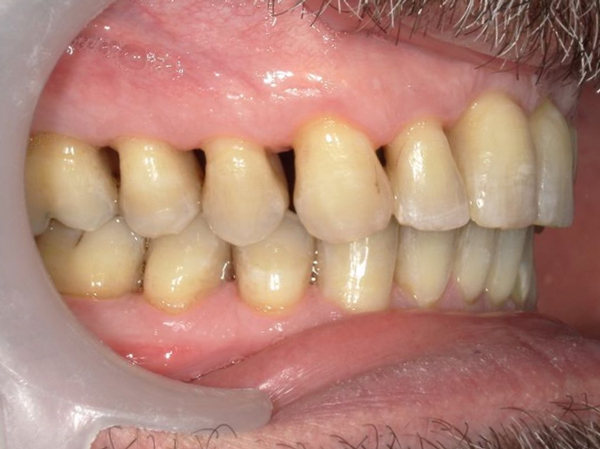

Présentation cas clinique :

Avant traitement

Après traitement